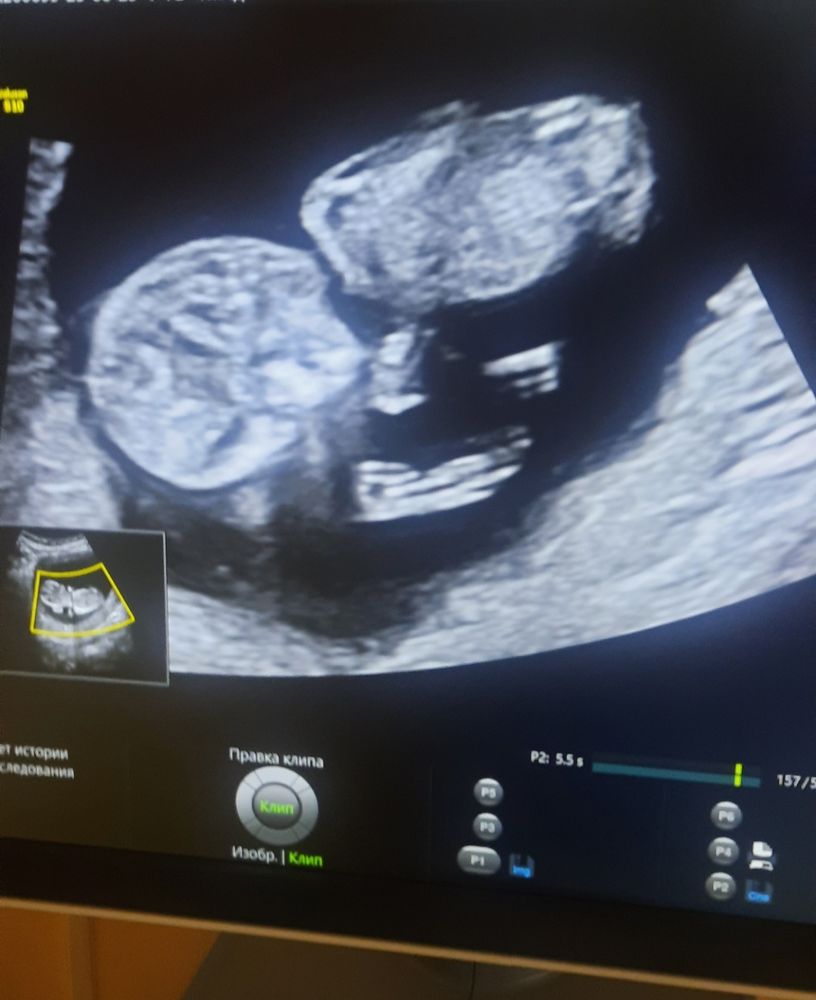

Девчат, по фото не видно пол? Ну а то некоторые по бугорку определяют, тут есть бугорок? Не спрашивала у врача, она какая то злюка была ))) Срок по мес 11,4 а по окружности головы и ктр 12,4.